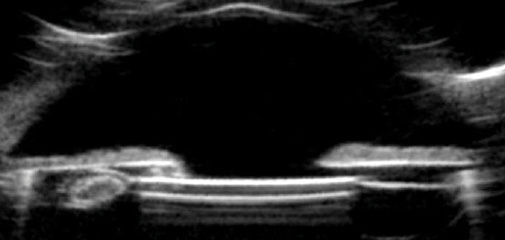

Figure 1. Slit-lamp retroillumination showed iris transillumination defects overlying the optic edge.

On examination, BCVA measured 20/30-2 in the affected eye. In the fellow eye, BCVA was 20/60, and there was amblyopia and an exotropia. The IOP measured 24 mm Hg OS on timolol, and the trabecular meshwork showed asymmetrically heavy pigmentation, with iris transillumination defects overlying the inferior optic edge (Figure 1). The IOL itself was mildly subluxated inferiorly, and ultrasound biomicroscopy (UBM) confirmed contact between the inferior iris and optic, with a Soemmering ring causing anterior displacement of the IOL (Figure 2). Visual field testing of the left eye demonstrated an early nasal step, and the optic nerve exhibited mild superior thinning.

Figure 2. In a vertical orientation (inferior angle is on the left), UBM demonstrated an inferiorly subluxated IOL, Soemmering ring, and optic-iris contact inferiorly.